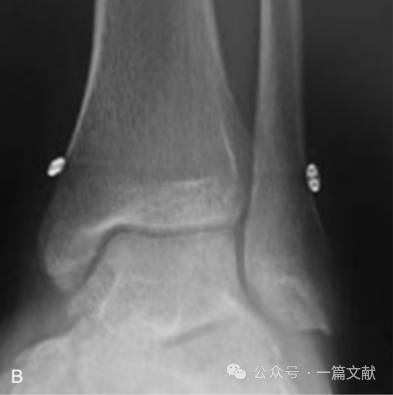

3,弹性固定:很多研究显示,相较于常规螺钉固定,弹性固定并没有明显优势。如下图,

图片